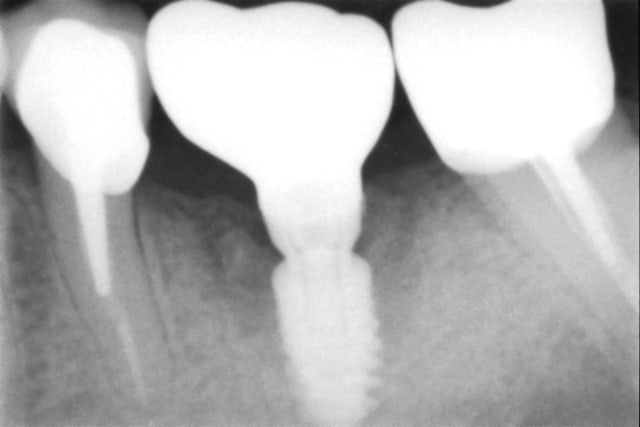

En illustration, j'ajoute des clichés pour RE expliquer pour ceux qu'on pas pigé que c'est opérateur dépendant.

cliché 1 : l'implant mésial a pas été assez enfoui, cratérisation distale (site d'extraction du jour de la pose)

cliché 2 : le pilier de droite est trop bas (pas de 3mm le jour de la pose, mais patient voulait une pro : mis un 1,5 angulé...bof). Sanction : ça commence à chier en mésial.

cliché 3 : enfouissement ok : quand c'est posé comme ça avec la bonne vis qui arrive à la bonne hauteur pour la prothèse définitive, on a JAMAIS de souci de "cratère"

cliché 4 : EII sur une 36, l'os a l'air de quand même bien aimer ce col quand la prothèse est à distance...

Moralité : c'est la prothèse qui dicte l'enfouissement, et pas le niveau osseux dispo. Mais ptêt que certains font autrement, après faut pas chercher pourquoi on cratérise : l'espace biologique.